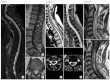

Methods: Forty-eight patients were treated for an intramedullary tumor between 2014 and 2020 at a single institution. Patients' files were retrospectively studied. We detailed clinical status according to neurological deficit and ambulatory ability using the modified McCormick Scale, radiological features like number of levels, associated syringomyelia, surgical technique with or without intraoperative electrophysiological monitoring, pathological findings, and postoperative outcome.

Results: The median age of this population was 43 years, including 5 patients under 18 years. The median delay before first neurosurgical contact was 3 months after the first clinical complaint. Treatment was gross total resection in 43.8%, subtotal resection in 50.0%, and biopsy in 6.2%. A laminectomy was performed for all the patients except 2 operated using the laminoplasty technique. Pathological findings were ependymoma in 43.8%, hemangioblastoma in 20.8%, and pilocytic astrocytoma in 10.4%. Six patients were reoperated for a tumor recurrence less than 2 years after the first surgical resection. One patient was reoperated for a postoperative cervical kyphosis.